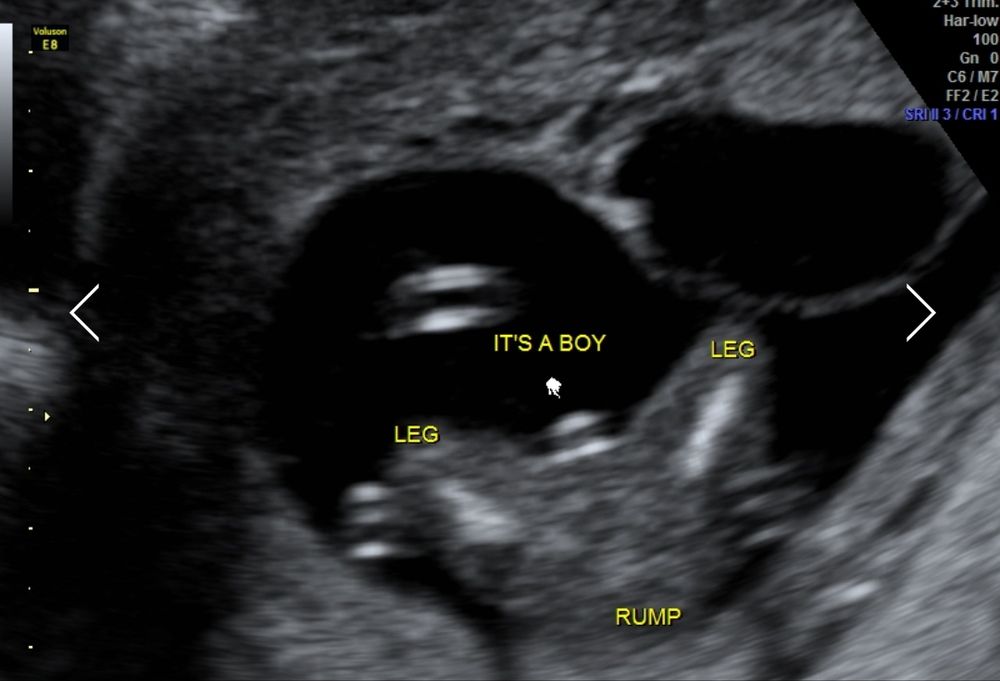

Каклетка с пюрешкой в Благополучная беременность год Пол ребенка 15+4 УЗИ, КТГ, доплер Ваше мнение? Мне на мальчика не очень похоже, будто пуповина 🙄 Посмотрите еще 20 записей на эту тему Лучший ответ Liza Kudrja Мальчик у вас, вот мой пацан на таком же сроке 16.08.2024 Ответить Отменить Ответить Юлия * Мальчик, у девочек все пусто на таком сроке, вот моя, одна из 😅 13.08.2024 Ответить Пума Мальчик😌 13.08.2024 Ответить Таня А мне очень даже похоже, что мальчик. Ракурс хороший 13.08.2024 Ответить Узи 15 недель Результат ктг Чаты Беременных Выберите чат: Январята-2026 Февралята-2026 Мартята-2026 Апрелята-2026 Майчата-2026 Июнята-2026 Июлята-2026 Августята-2026